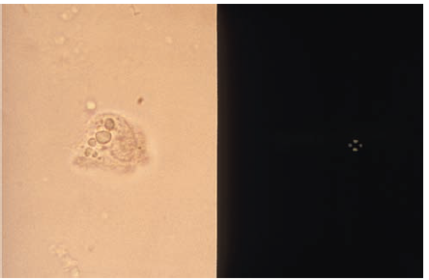

| Oval fat body (bright field on right and polarized on left (notice the Maltese cross)) | |